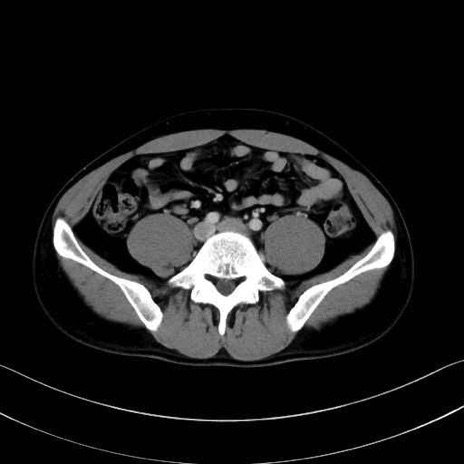

大腰筋 (Psoas major)

腸骨筋 (Iliacus)